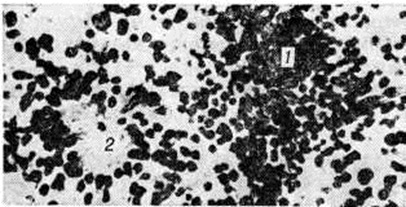

НейробластомаНейробластома (neuroblastoma; греческий neuron нерв + blastos росток -oma) — злокачественная дизонтогенетическая опухоль, состоящая из незрелых клеток ганглиозно-клеточного ряда. Классификация ганглиозно-клеточных опухолей трудна, так как в одной и той же опухоли нередко определяются элементы различной степени зрелости. В связи с этим Уиллис (R. Willis) предлагает пользоваться термином «Нейробластома» как обобщающим и наиболее простым. Нейробластома встречаются редко, преимущественно в детском и юношеском возрасте. По локализации различают Нейробластома головного мозга и Нейробластома, исходящие из элементов симпатической части высшая нервная система Патологическая анатомия. Из Нейробластома головного мозга описаны Нейробластома области серого бугра и третьего желудочка, белого вещества полушарий большого мозга, мозжечка. Макроскопически опухоль имеет вид узла серо-розового цвета диаметром от 1 до 1,5 сантиметров на разрезе ткань опухоли пористая, нередко с кистами. Микроскопически Нейробластома состоит из довольно плотно примыкающих друг к другу клеток, местами с образованием розеток, состоящих из безотростчатых аполярных нейробластов, выявляемых при импрегнации по Бильшовскому — Грос — Лаврентьеву. Опухолевые клетки представлены нейробластами различной степени зрелости, вплоть до зрелых ганглиозных клеток с нисслевской зернистостью в цитоплазме. Ядра опухолевых клеток пузырьковидные, различны по величине, с чётким темно-окрашенным ядрышком (рисунок 1). Соединительнотканная строма развита слабо. В ткани опухоли встречаются митозы, некрозы. Рост Нейробластома инфильтративный с неглубоким прорастанием окружающей ткани. Нейробластома симпатической части век н. с. исходят из крупных симпатических узлов и мелких интрамуральных ганглиев внутренних органов, а также из мозгового слоя надпочечников. Макроскопически они имеют вид узлов различной величины и окраски. В ткани опухоли встречаются очаги некроза. По степени зрелости среди Нейробластома симпатической части век н. с. различают симпатогониомы и симпатобластомы. Симпатогониома — наиболее злокачественная, незрелая, примитивная опухоль; встречается у новорожденных и в раннем детском возрасте. Опухолевые клетки — со скудной цитоплазмой и округлым темным ядром, напоминающим лимфоцит. Иногда встречаются псевдорозетки (рисунок 2). Эти клетки происходят из примитивных клеток — симпатогоний, отсюда термин «симпатогониома». Симпатобластома — более дифференцированная опухоль. Она содержит отростчатые нейробласты с крупными телами овальной, вытянутой иди полигональной формы, с пузырьковидным ядром, содержащим глыбки хроматина в виде спиц в колесе. Располагаются клетки плотно, иногда в виде тяжей, колонн, пучков. В ряде случаев встречаются ложные или истинные розетки (рисунок 3), некротические очаги. Разграничить симпатогониомы и симпатобластомы не всегда удаётся: такие опухоли, согласно номенклатуре ВОЗ, обозначают как нейробластомы. Клиническая картина. Нейробластома— злокачественные опухоли, дающие метастазы в пределах центральная нервная система и за её пределами, размеры метастазов нередко превышают размеры основного опухолевого узла. Эти опухоли часто рецидивируют. Клинические, картина Нейробластома головного мозга зависит от локализации опухоли и характера метастазирования (смотри полный свод знаний Головной мозг, опухоли). Нейробластома симпатической части век н. с. резко злокачественны, дают метастазы во внутренние органы и кости грудной клетки, черепа (симпатогониомы в 80% случаев). Клинические, картина весьма разнообразна. В частности, описаны две своеобразные формы симпатогониомы, происходящей из мозгового вещества надпочечников, известные как синдром Пеппера и синдром Гетчинсона. При синдроме Пеппера (описан в 1901 г.) опухоль метастазирует по лимфатических, путям преимущественно в органы брюшной полости. В раннем детском или грудном возрасте, иногда с рождения, отмечается резко прогрессирующая гепатомегалия, прощупываются подкожные узелки метастазов. Быстро наступают анемия, кахексия, резко ускоряется РОЭ. Течение характеризуется обострениями с периодами лихорадки. При синдроме Гетчинсона (описан в 1907 г.) опухоль метастазирует преимущественно в кости (основание черепа, длинные трубчатые кости). |

Рис. 2. | ||